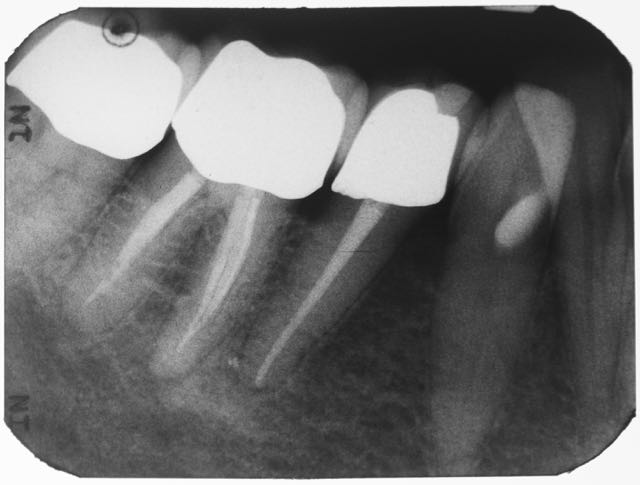

Sicherlich eignet sich nicht jede Wurzelbehandlung für ein single-visit-treatment. Zum einen läßt der ein oder andere Fall keine andere Wahl, da beispielsweise der Wurzelkanal in Vorbereitung der Wurzelfüllung nicht zu trocknen ist. Zum anderen sind bei Behandlungsumfänge jenseits der 90 Minuten für manch einen Patienten kaum auszuhalten. Die Behandlungs muss also zweigeteilt werden. Kleine Backenzähne wie im folgenden einer dargestellt oder Frontzähne sind fast prädestiniert für einzeitige Behandlungen. Der Fall dieses kleinen Backenzahnes mit einer lateralen Aufhellung ist ein Beispiel dafür. Der große schwarze Fleck rechts neben der Wurzel, ein apikales Granulom oder Entzündungsherd, war zur Nachkorntrolle so gut wie vollständig ausgeheilt.